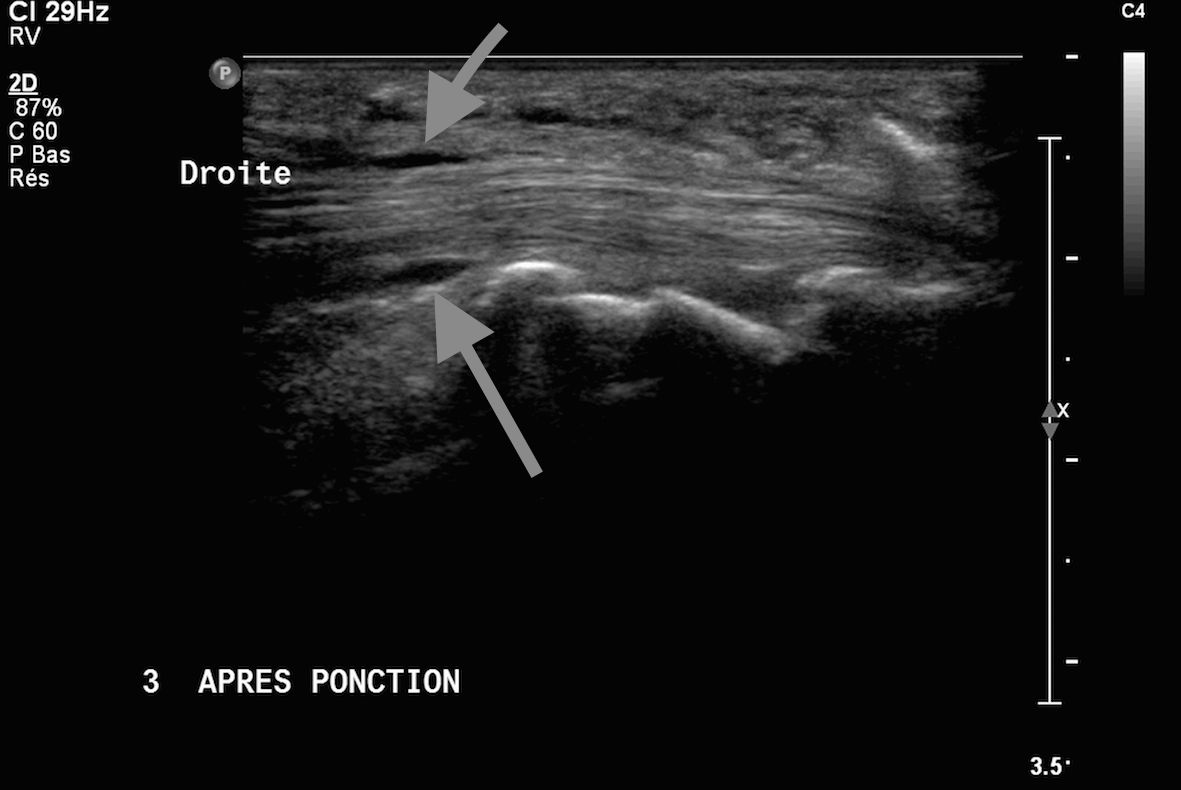

4Infiltration du tendon du tendon 3ième fléchisseur de la main (images 1 et 2) sous contrôle échographique

Images 3 et 4 visibilité du produit anti inflammatoire injecté sous deux incidences orthogonales en regard de la gaine péri tendineuse